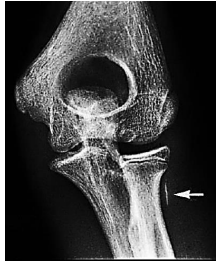

Artefatos são características visuais falsas em uma imagem médica que distorcem a interpretação do exame, levando a diagnósticos imprecisos. Observe a imagem a seguir.

Na imagem, a seta indica um artefato causado por